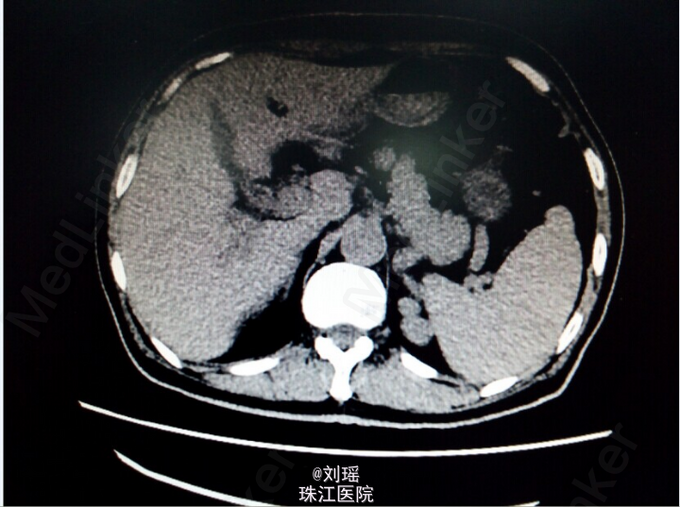

查体:生命体征平稳,慢性病容,皮肤巩膜重度黄染,右上腹T管,余无特殊。 辅助检查: 肝胆脾CT:右肾囊肿;胆总管粘液腺癌术后。 T管造影:胆总管全段可见不同程度,不同大小之充盈缺损并不同程度狭窄,考虑为占位性病变。肝内胆管明显扩张。